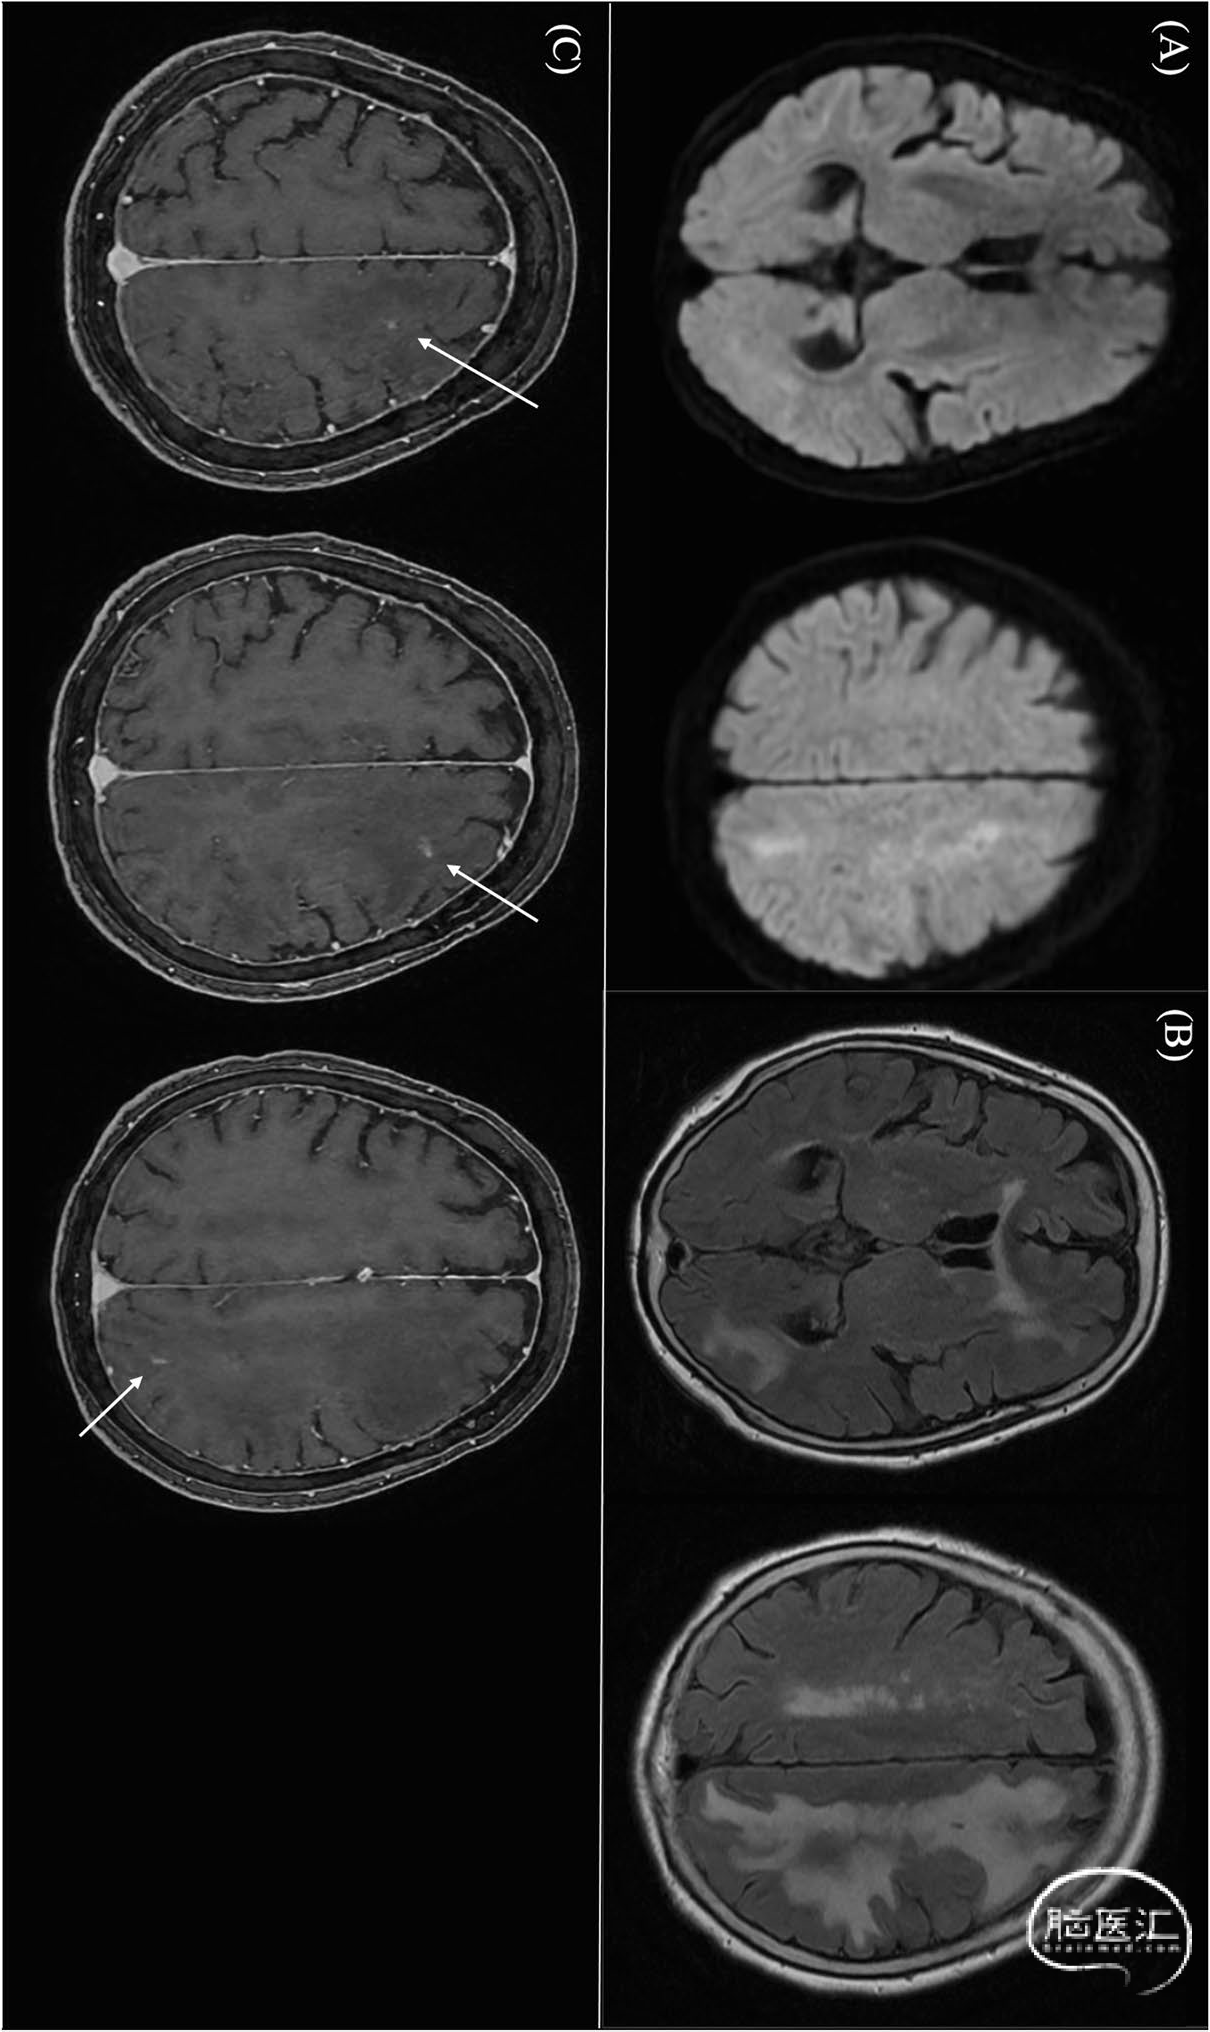

图1,术后3个月磁共振成像。A,左半球没有新的脑梗死。B,Flair显示左半球重度脑水肿。C,增强磁共振成像显示左半球有一些小的强化病灶(白色箭头):

78岁女性,既往有高血压、深静脉血栓形成和结直肠癌病史,通过pipeline栓塞装置(pipeline embolization device,PED;Medtronic,Irvine,CA,USA)治疗左侧颈内动脉瘤。阿司匹林和氯吡格雷用于择期PED放置。尽管术后早期MRI显示左半球微梗塞,无神经功能缺损,但患者在术后3个月出现间歇性头痛和记忆障碍。复查影像学检查显示左大脑半球有多个T1强化病灶和广泛的T2高信号异常,提示存在栓塞或异物反应(图1)。由于担心患者CYP2C19代谢状态,把氯吡格雷替换成普拉格雷。